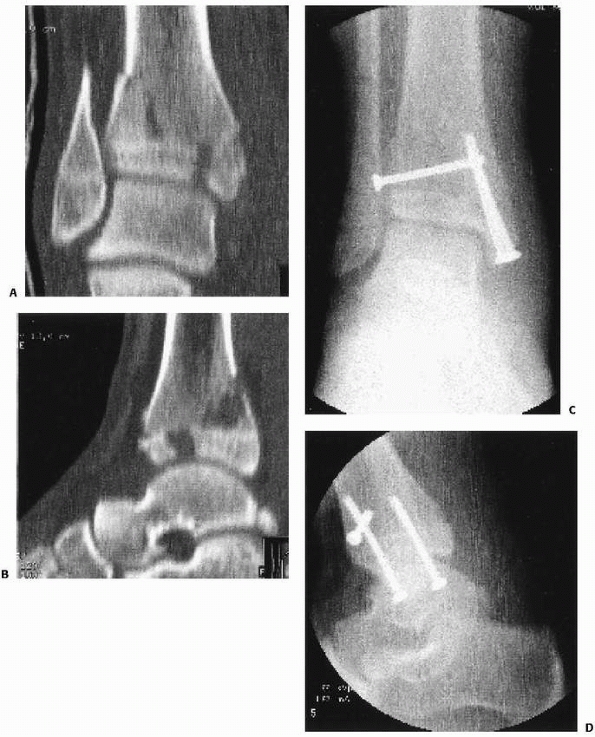

FIGURE 26-21 Coronal and sagittal CT images of Tillaux fracture A. CT scan sagittal image of juvenile Tillaux fracture. Note the degree of intra-articular displacement. B. CT scan coronal image of juvenile Tillaux fracture. C. CT scan can facilitate screw placement/orientation. D. Reduction with intraepiphyseal screws.

|

common the appearance of a Salter-Harris type III fracture on the

the lateral radiographs (Fig. 26-11). CT scans can be very helpful to understand the complex anatomy of these fractures (see Fig. 26-11). It has been proposed that the mechanism of injury for Tillaux and triplane fractures is external rotation.47,148

in place.165 Screw fixation within the epiphysis is usually adequate (see Fig. 26-21 and section on arthroscopic treatment of intra-articular fractures).